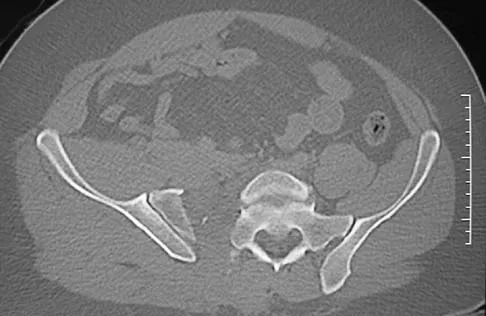

A paraplegic 32-year-old man was pulling himself up in bed by grasping the headboard rails when he felt a pop and immediate pain. A radiograph and CT scan are shown in Figures 2a and 2b. Based on these findings, management should consist of

Explanation

The coracoid process is an essential component of the superior shoulder suspensory complex and must be maintained. Open reduction and internal fixation is recommended if the fragment is large and displaced more than 1 cm. Froimson AI: Fracture of the coracoid process of the scapula. J Bone Joint Surg Am 1978;60:710-711.